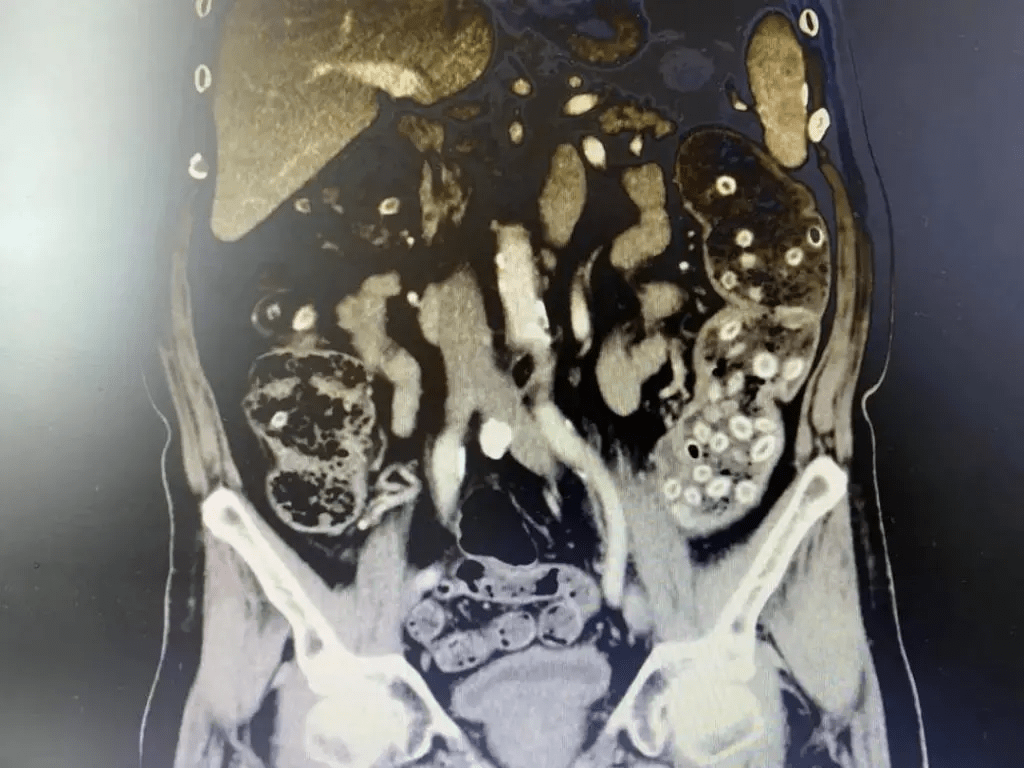

刘杰峰主任接诊后 , 给唐爹爹完善 CT 简直 " 惊呆了 "!一肚子密密麻麻的小 " 珠珠 " 仿佛连成一串 " 珍珠项链 " 了 。

文章图片